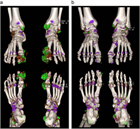

1. 痛風の確定診断は関節液中の白血球に貪食された尿酸―ナトリウム結晶の検出による(推奨度2)(JG)[1]